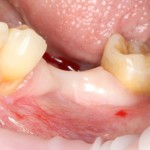

Через 4 месяца мы можем оценить результат проведенной операции:

A09A6611 (2) A09A6612 (2)

На фотографиях видно, насколько атрофировался костный блок. Именно поэтому при планировании мы увеличили объемы блока на величину этой атрофии.

Удаляем винты. Для этого не нужно делать больших разрезов:

A09A6617 (2)

Иногда винты остеоинтегрируются как импланты. Можно их оставить, ничего страшного в этом нет.

Теперь делаем разрез и открываем импланты:

A09A6620 (2) A09A6621 (2)

На фотографиях хорошо видно, какие изменения произошли с областью операции за четыре месяца. Пересаженный костный блок интегрировался настолько хорошо, что частично заросли заглушки имплантов. Такое нередко происходит, именно поэтому в подобных случаях я предпочитаю импланты с конической ортопедической платформой — их легче открывать.

Нам остается просто поставить формирователи десны:

A09A6628 (2) A09A6629 (2)

и подождать, пока вокруг них сформируется плотная слизистая оболочка. Потом мы направляем пациента к ортопеду для протезирования.